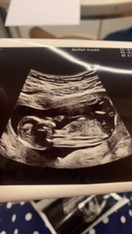

ใช่แขนขาน้องรึป่าว หรือเราคิดไปเอง🥰😂ซาวตอน18+3

13w ค่ะ ทำท่าเหมือนจะดูดนิ้วเลยค่ะ 🥰